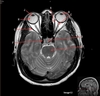

Image weighting and axis

T2 Axial

A

Caudate Nucleus

B

Thalamus

C

Third ventricle

D

Lentiform Nucleus

E

Frontal Sinus